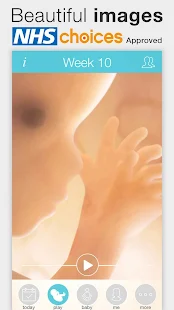

Pregnant? Get the worldwide No.1 Pregnancy App. Approved by the NHSWant to see beautiful, interactive images for every week of your pregnancy? Join more than 4 million users who already use this Pregnancy App to follow their pregnancy.

Our Pregnancy+ App can also be personalized for dads, grandparents and other family members.

Many happy parents and healthcare providers find this App easy to use and very informative.

- Pregnancy week by week info